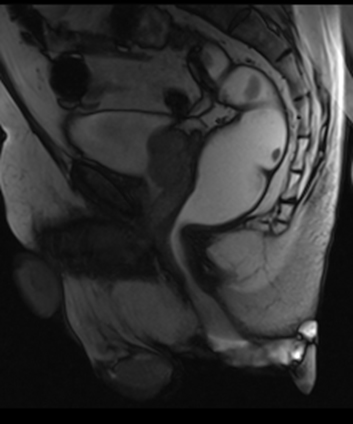

La defecografía es una técnica mínimamente invasiva, bien tolerada por el paciente y permite obtener información sobre el músculo del esfínter anal, el músculo puborrectal y elvedador del ano, así como también el estudio de la función rectal y de la anatomía rectal patológica.

Se trata de una exploración dinámica. Consiste en la administración de un producto baritado que provoca la opacificación del recto y permite la evaluación mediante radioscopia de la evacuación.

La defecografía pone en evidencia las anomalías estáticas y dinámicas de la incontinencia.

Los hallazgos más comúnmente encontrados son el rectocele, enterocele y la intususpección rectal.

Como complemento para el diagnóstico resulta de interés la medición de los ángulos anorrectales en situación de reposo y retención.